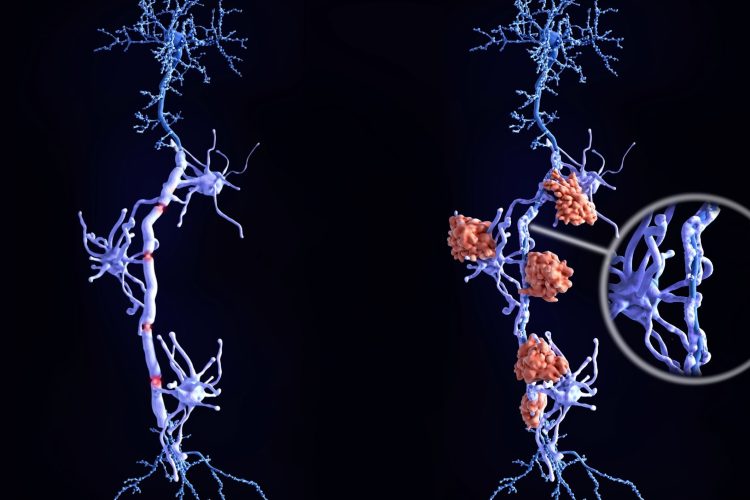

Το tolebrutinib είναι ένα από του στόματος φάρμακο που ανήκει σε μια νέα κατηγορία θεραπειών, τους αναστολείς BTK (Bruton’s Tyrosine Kinase). Σε αντίθεση με πολλές υπάρχουσες αγωγές που δρουν κυρίως στο ανοσοποιητικό σύστημα εκτός εγκεφάλου, το tolebrutinib έχει σχεδιαστεί ώστε να δρα και μέσα στο κεντρικό νευρικό σύστημα.

Αυτό έχει ιδιαίτερη σημασία για άτομα με μη υποτροπιάζουσα δευτερογενώς προοδευτική ΣΚΠ, μια μορφή της νόσου όπου τα συμπτώματα επιδεινώνονται αργά αλλά σταθερά, επηρεάζοντας την κινητικότητα, την αυτονομία και την καθημερινότητα.